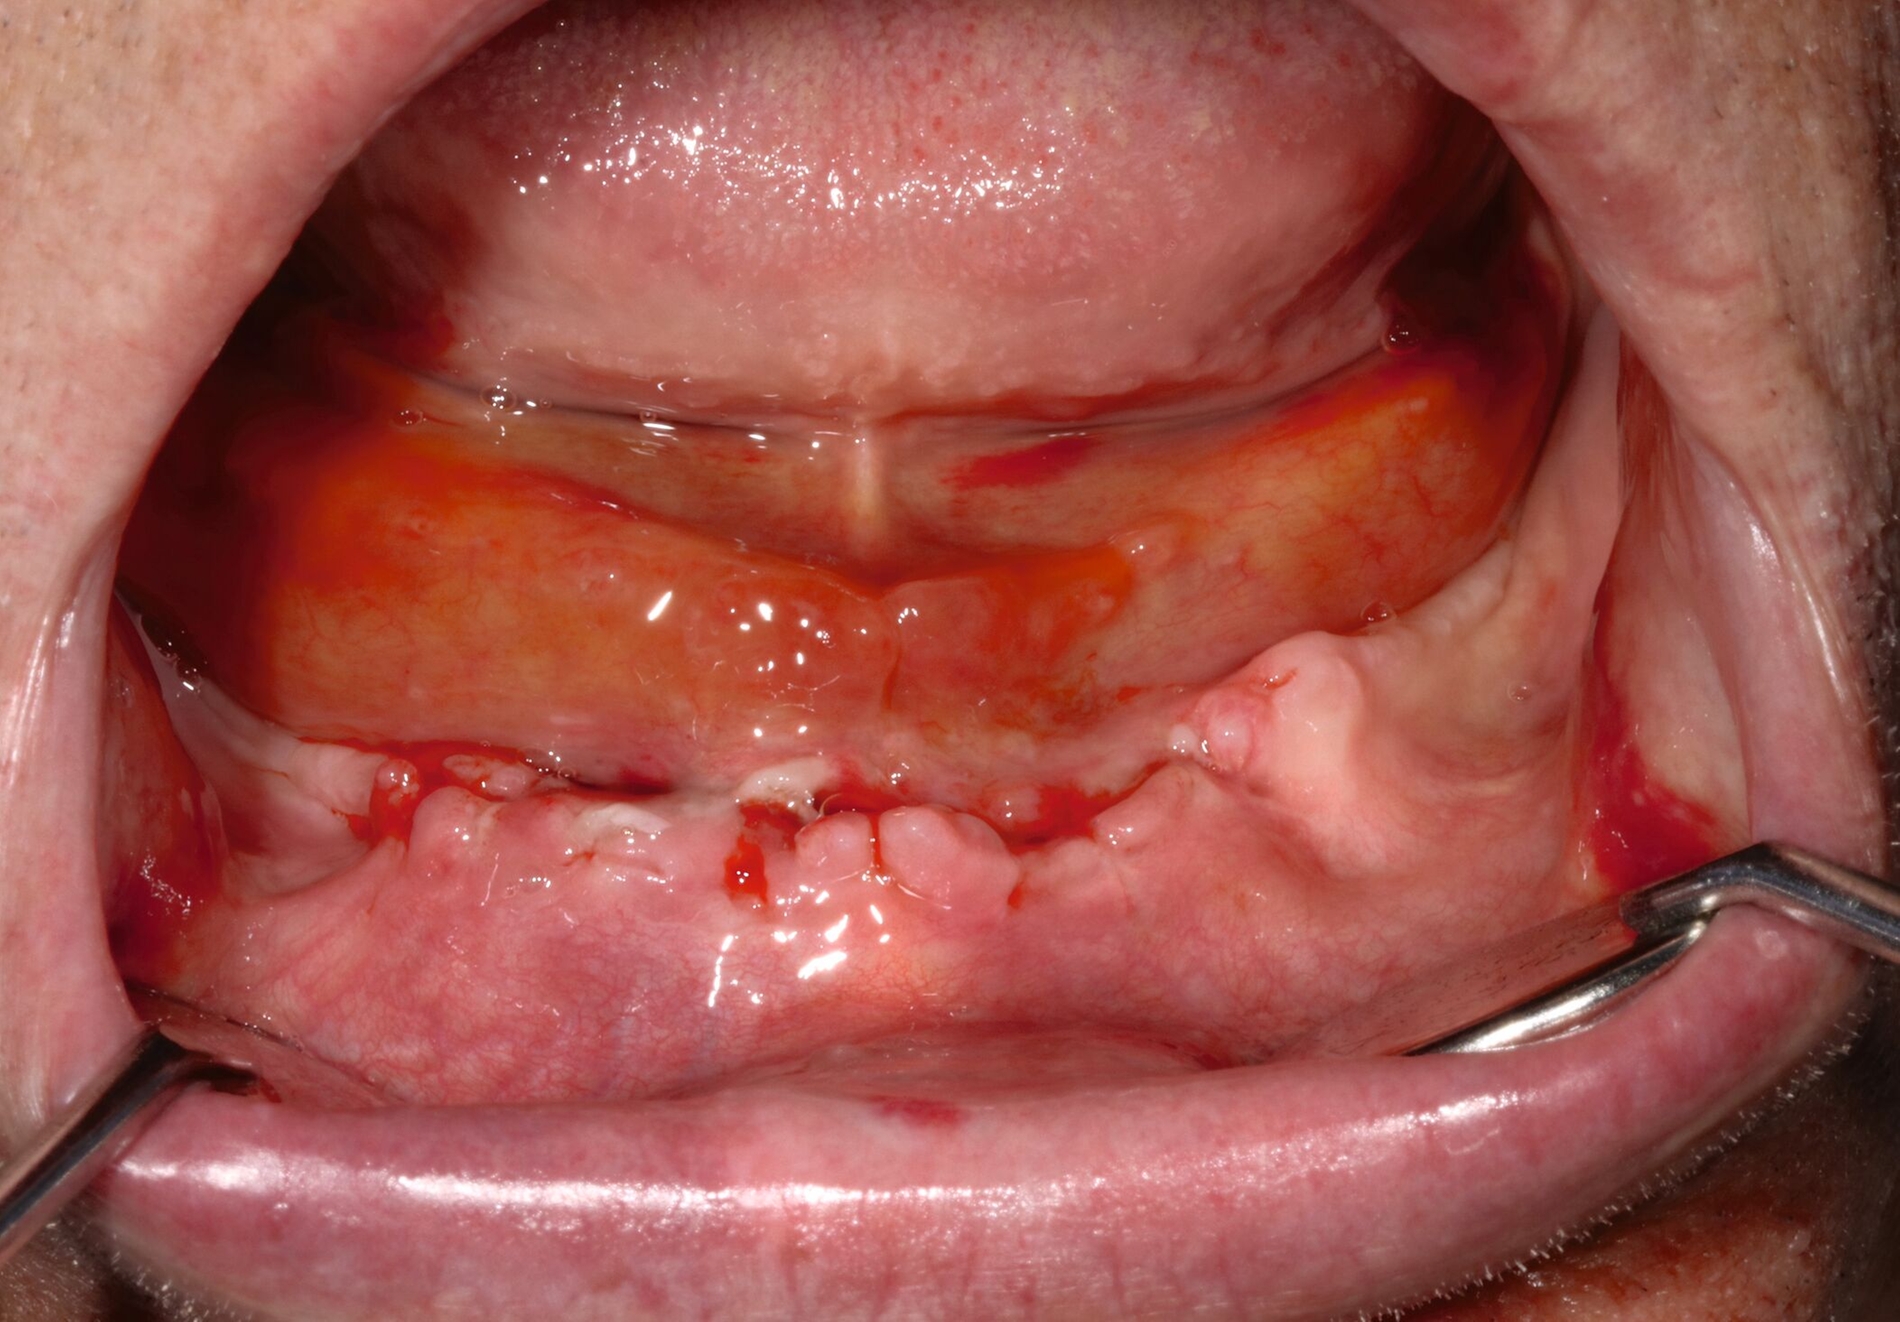

Therapeutisch erfolgten als abschwellende Maßnahmen die Applikation von lokaler Kälte sowie die Gabe von Dexamethason für insgesamt drei Tage (8 mg – 8 mg – 8 mg; 4 mg – 4 mg – 4 mg; 2 mg – 2 mg – 2 mg). Des Weiteren erhielt der Patient eine intravenöse Antibiose zur Infektionsprophylaxe mittels Sultamicillin (3 x 3 g/d für vier Tage) sowie für weitere drei Tage peroral mittels Amoxicillin/Clavulansäure (875/125 mg 2 x 1 Tablette/d). Ergänzend erfolgten eine adaptierte orale Schmerztherapie mittels Metamizol (3 x 30 gtt/d), die Umstellung auf flüssige Kost sowie tägliche Wundkontrollen und Reinigungen mittels Chlorhexamed-Mundspüllösung 0,2 Prozent. Darunter zeigten sich ein rascher Rückgang des Hämatoms und eine zeitgerechte Abheilung der Implantatinsertionsstellen im weiteren stationären Verlauf (Abbildung 4), sodass der Patienten nach viertägiger Überwachung mit einer geringen Restschwellung / einem geringen Resthämatom und ohne klinische Beschwerden in die ambulante Nachsorge entlassen werden konnten (Abbildung 5). Während der ambulanten Nachkontrollen zeigte sich eine vollständige Regression der Beschwerden.